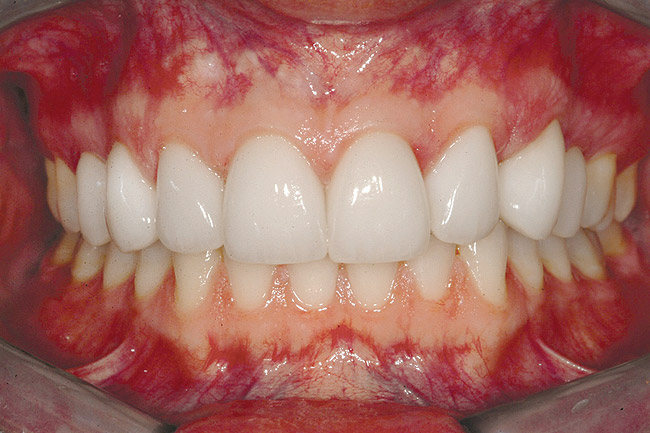

Fig 6 (and Fig 7). Prerestorative orthodontics was completed in 5 months. Final result 3 years, 4 months after completion.

Figure 6

Fig 7 (and Fig 6). Prerestorative orthodontics was completed in 5 months. Final result 3 years, 4 months after completion.

Figure 7

Fig 8 (and Fig 9). Teeth Nos. 5 and 12 were converted to Nos. 6 and 11, and Nos. 6 and 11 were converted to Nos. 7 and 10. Nos. 4 and 13 were enlarged. Note stability and absence of orthodontic relapse. Before-and-after smiles. Periodontist: Edward P. Allen, DDS, PhD. Prosthodontist: Robert R. Winter, DDS.

Figure 8

Fig 9 (and Fig 8). Teeth Nos. 5 and 12 were converted to Nos. 6 and 11, and Nos. 6 and 11 were converted to Nos. 7 and 10. Nos. 4 and 13 were enlarged. Note stability and absence of orthodontic relapse. Before-and-after smiles. Periodontist: Edward P. Allen, DDS, PhD. Prosthodontist: Robert R. Winter, DDS.

Figure 9